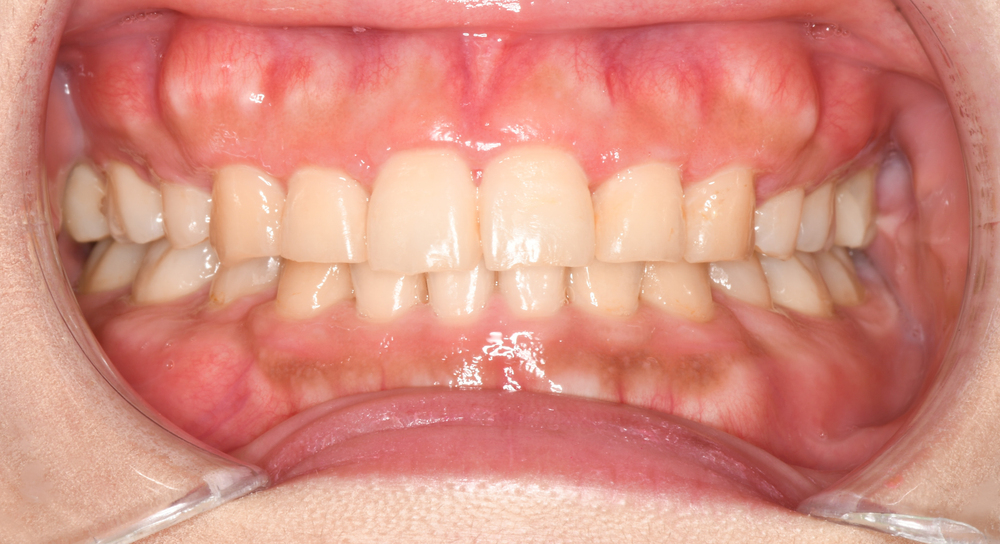

口腔内の写真です。まずは正面です。

上下顎の正中線も顔面正中を基準にぴったりと合っています。

また個々の歯の位置異常が適切に整えられていることがお分かりいただけると思います。

右側です。

上下顎前歯の唇側傾斜が改善され理想的な歯軸傾斜と上下的なかみ合わせを獲得することが出来ました。